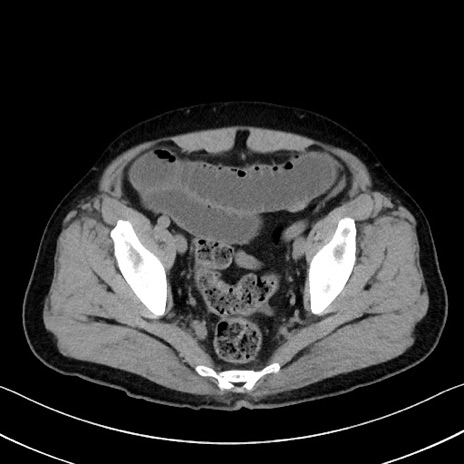

症例35(横断像)

【症例】70歳代 男性

【主訴】腹部膨満、嘔吐

【現病歴】昨日より腹部膨満感出現。本日増悪し、仙痛出現。嘔吐あり、受診。

【既往歴】糖尿病、胆摘後

【身体所見】BP 149/80mmHg、HR 74/min、BT 35.9℃、腹部:膨満、軟、圧痛なし。腸雑音減弱あり。上腹部正中切開瘢痕あり。

【データ】WBC 13500、CRP 1.72